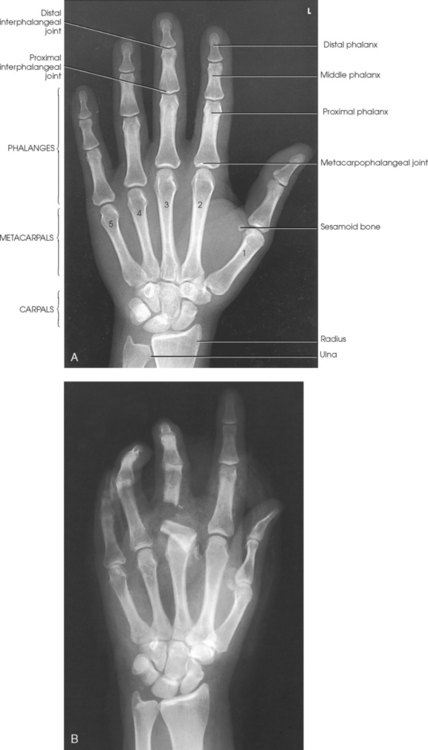

The hand consists of 27 bones, which are subdivided into the following groups:

• Phalanges: Bones of the digits (fingers and thumb)

• Metacarpals: Bones of the palm

• Carpals: Bones of the wrist (Fig. 4-1)

The digits contain 14 phalanges (phalanx, singular), which are long bones that consist of a cylindric body and articular ends. Nine phalanges have two articular ends. The first digit has two phalanges—the proximal and distal. The other digits have three phalanges—the proximal, middle, and distal. The proximal phalanges are the closest to the palm, and the distal phalanges are the farthest from the palm. The distal phalanges are small and flattened, with a roughened rim around their distal anterior end; this gives them a spatulalike appearance. Each phalanx has a head, body, and base.

Five metacarpals, which are cylindric in shape and slightly concave anteriorly, form the palm of the hand (see Fig. 4-1). They are long bones consisting of a body and two articular ends—the head distally and the base proximally. The area below the head is the neck where fractures often occur. The first metacarpal contains two small sesamoid bones on its palmar aspect below the neck (see Fig. 4-1). A single sesamoid is often seen at this same level on the second metacarpal. The metacarpal heads, commonly known as the knuckles, are visible on the dorsal hand in flexion. The metacarpals are also numbered 1 to 5, beginning from the lateral side of the hand.

The wrist has eight carpal bones, which are fitted closely together and arranged in two horizontal rows (see Fig. 4-1). The carpals are classified as short bones and are composed largely of cancellous tissue with an outer layer of compact bony tissue. These bones, with one exception, have two or three names; this atlas uses the preferred terms (see box). The proximal row of carpals, which is nearest the forearm, contains the scaphoid, lunate, triquetrum, and pisiform. The distal row includes the trapezium, trapezoid, capitate, and hamate.

Fig. 4-9 A, Articulations of hand and wrist. B, Radiocarpal articulation formed by scaphoid, lunate, and triquetrum with radius. C, Coronal MRI of wrist showing bones and joints of wrist.

The carpals articulate with each other, the metacarpals, and the radius of the forearm. In the carpometacarpal (CMC) articulations, the first metacarpal and trapezium form a synovial saddle joint, which permits the thumb to oppose the fingers (touch the fingertips). The articulations between the second, third, fourth, and fifth metacarpals and the trapezoid, capitate, and hamate form synovial gliding joints. The intercarpal articulations are also synovial gliding joints. The articulations between the lunate and scaphoid form a gliding joint. The radiocarpal articulation is a synovial ellipsoidal type. This joint is formed by the articulation of the scaphoid, lunate, and triquetrum, with the radius and the articular disk just distal to the ulna (Fig. 4-9, C).